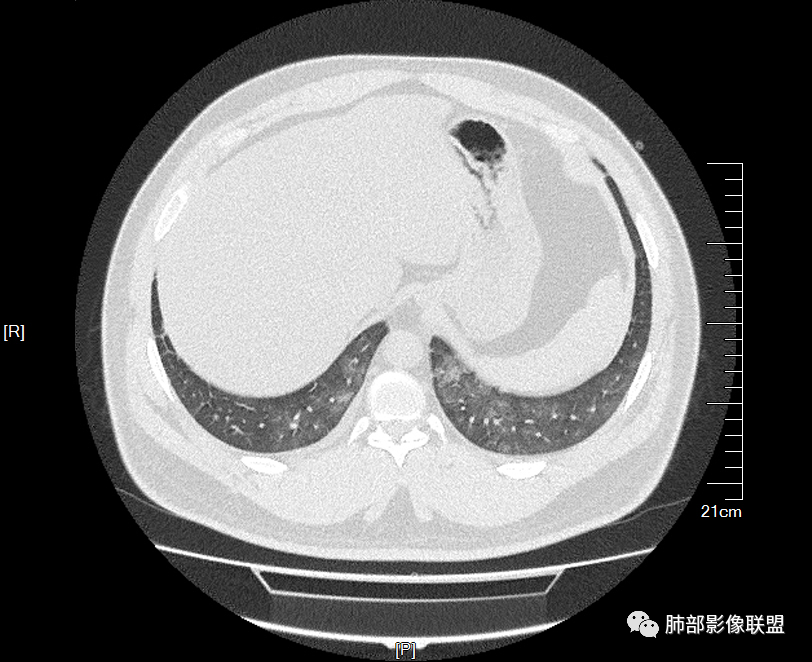

痛风入院。无肺部症状

多发GGO结节,边界清,以全小叶、小叶中心为主:

GGO背景

小叶间隔增厚,无明显重力趋势

少量积液,脂肪肝

这里有一点重力趋势

中轴间质稍增厚

细网格也明显

中轴间质增厚,小叶间隔增厚,小叶内间质增厚,部分重力作用,双侧对称,胸水,按理淋巴道回流受阻有

肺水肿类病变有

问题是腺泡结节如何解释?